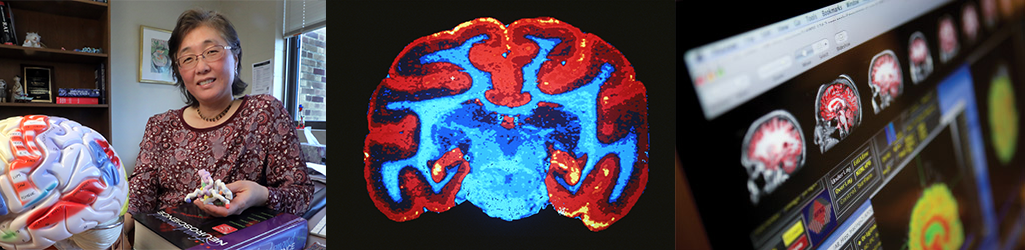

Specialize in cellular and molecular neuroscience

Students pursuing this specialization will use neuroscience approaches to understand neural function and pathology in animal and cellular models. Applicants who are well-suited to this track are those with interests in acquiring skills using techniques in animal models to understand mechanisms of behavior and brain function.